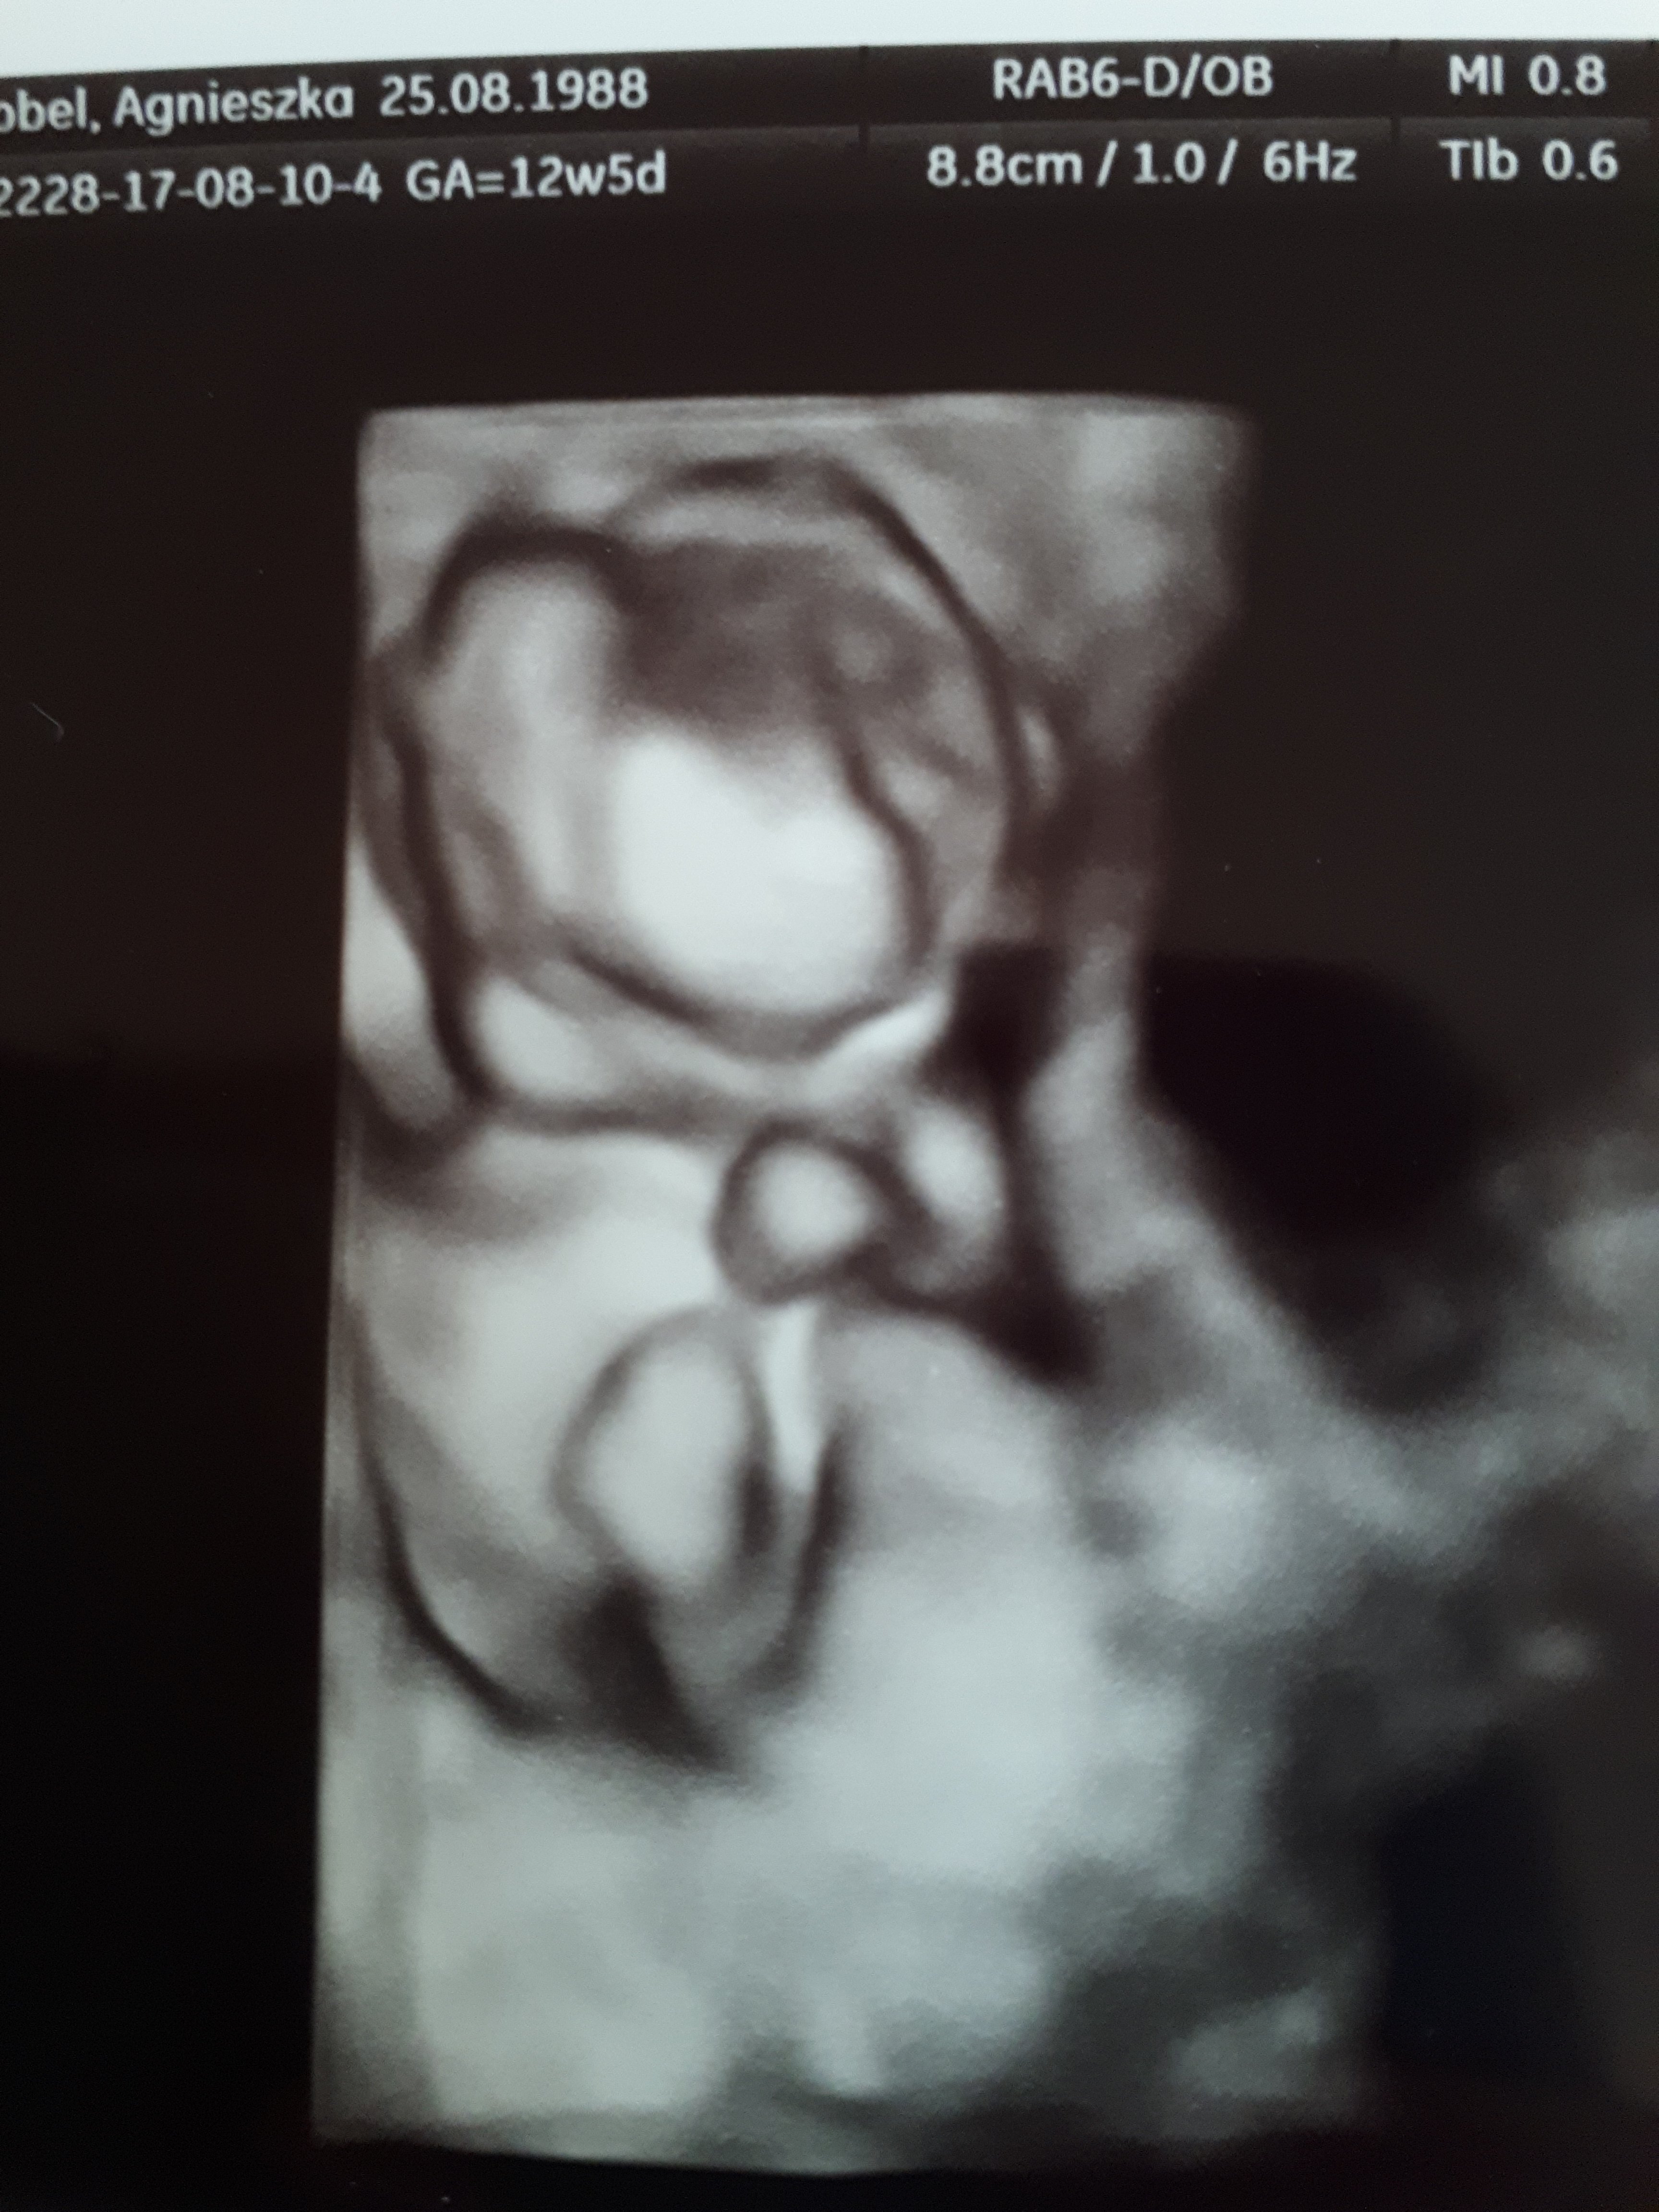

A tu nasz robaczek

Dzidzius zdrowiutki fika jak szalony i mamy juz 7cm

Na 99% chlopczyk ale na 100% na nastepnej wizycie 28 wrzesnia bedzie wiadomo